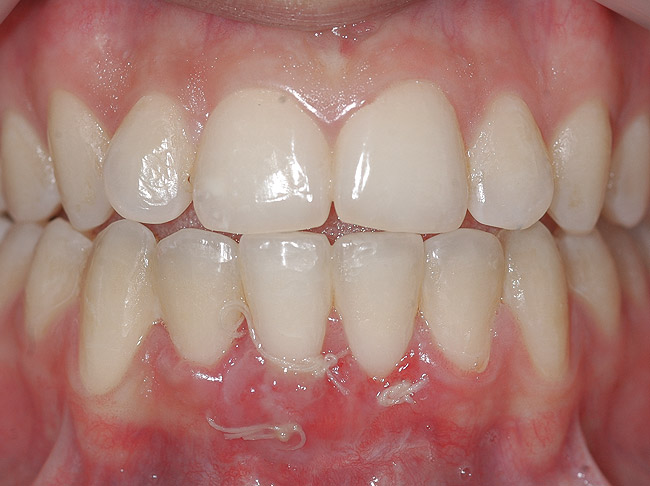

CASE 1 Fig 2. Pre-treatment clinical view of a 28-year-old patient with Miller Class I recession of the lower left central incisor treated with conservative SPT.

Figure 2

Fig 3. Two-year follow-up of same patient shows spontaneous root coverage.

Figure 3